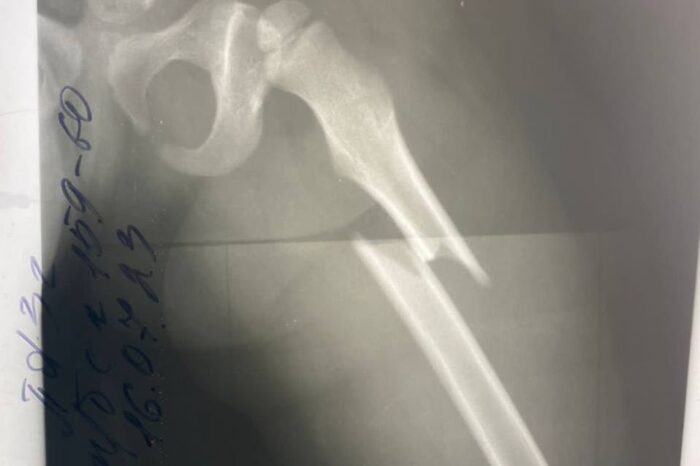

У маленькой девочки диагностировали закрытый перелом левого бедра со смещением отломков.

У маленькой девочки диагностировали закрытый перелом левого бедра со смещением отломков. Врачи смогли избежать лечения со скелетным вытяжением.

Ребенка успешно прооперировали и установили металлическую конструкцию. На пятые сутки малышку уже выписали. Через несколько недель девочке разрешат нагрузку на ногу, а через год удалят металлоконструкцию из бедра.

Медики подчеркивают, что раньше такие случаи у детей лечились на скелетном вытяжении в течение полутора месяцев. Сегодня новые методики позволяют даже не накладывать гипс, так как перелом срастается быстрее.